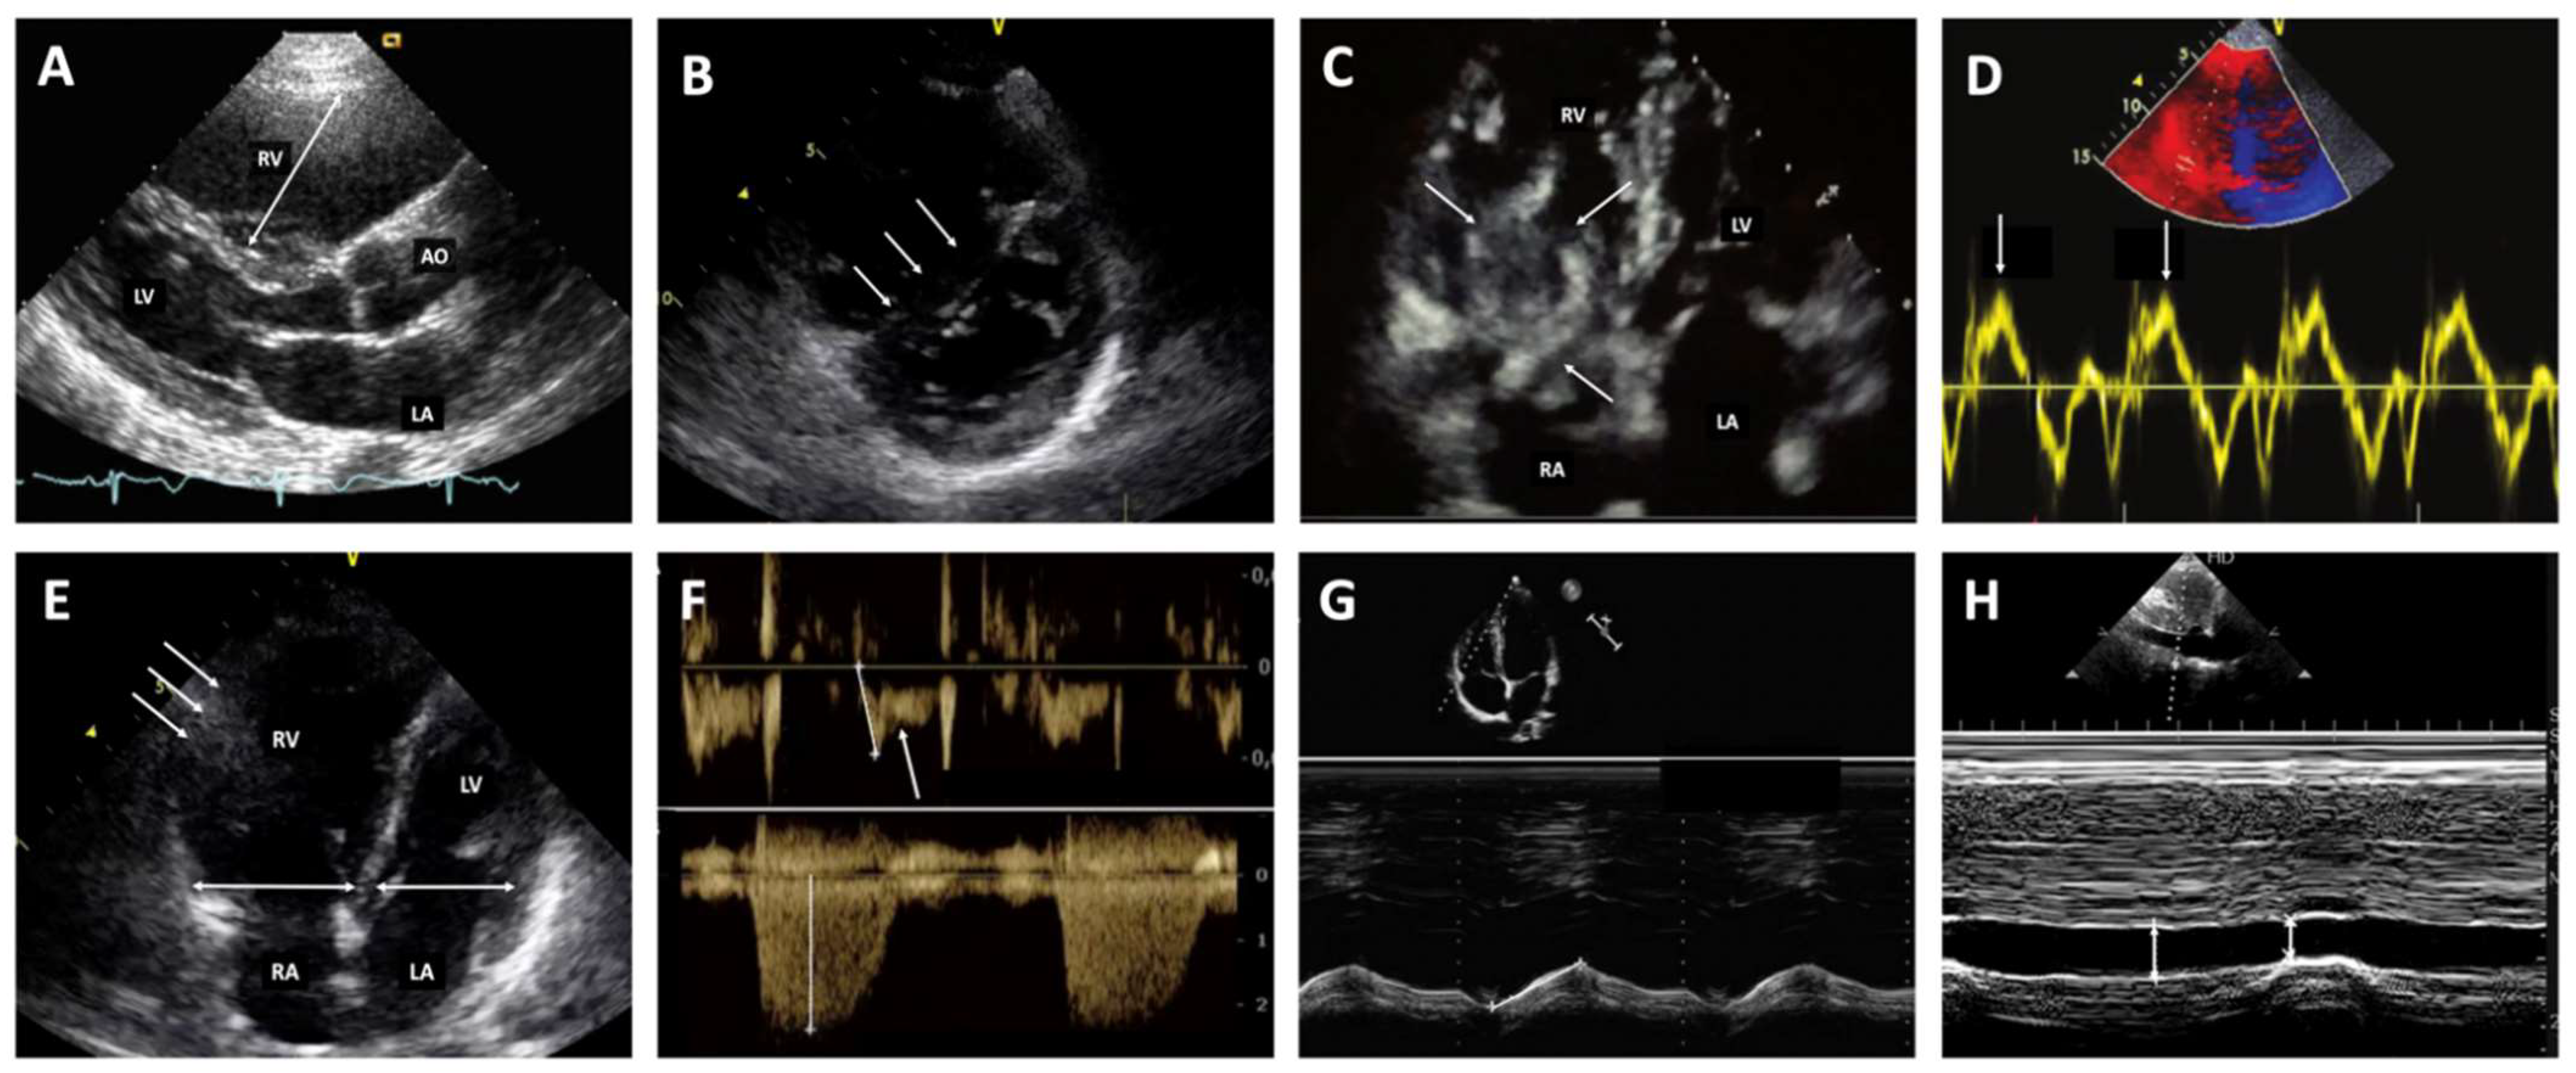

3.2. Diagnostic Strategy